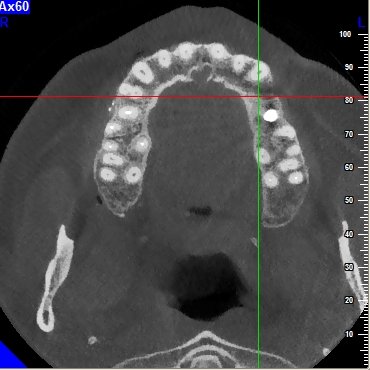

Lo studio radiografico evidenzia un' atrofia ossea di tipo passante con direzione cranio-buccale verso caudo-palatale

assiali

post-729-0-81886500-1390144132_thumb.jpg

post-729-0-34906200-1390144147_thumb.jpg